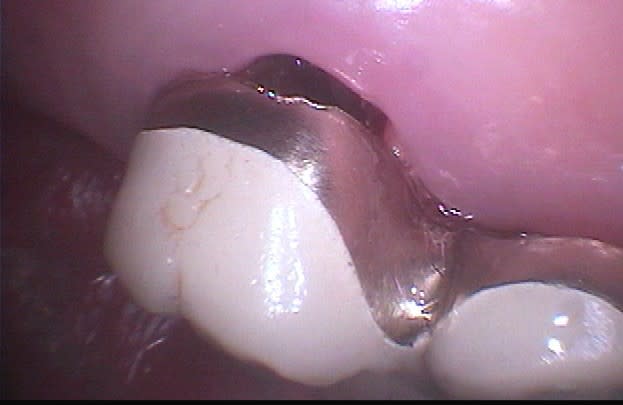

Voici un cas moins gentil avec élimination de la cause du problème pour reprendre les termes de Marc.

Il s'agit d'une patiente de 90 ans sur qui je reconstituais les secteurs postérieurs mandibulaires, ce qui fera l'objet d'un prochain post d'ailleurs, et dont un simple détartrage révélait la présence d'une énorme carie sous le pilier distal d'un bridge reliant la 23 à la 26.

Ayant intérêt à éviter de commencer un gros chantier alors qu'un autre était en cours, j'ai opté pour dégager et éliminer cette carie en conservant provisoirement ce bridge qui tenait bien, avant de traiter ce secteur en tachant de récupérer la racine de la 26 si possible.

J'ai déjà récupéré de nombreuses racines à ce stade et les ai utilisées comme piliers de bridges ou les ai couronnées, dans la mesure ou l'ancrage alvéolaire était solide et en respectant les furcations pour y assurer l'hygiène.

La gencive lasérisée devient très ferme avec le temps et le déchaussement se stabilise. Ces restaurations se comportent bien sur un recul de plusieurs années.

Un exemple: une 46 avec furcation linguale dénudée après lasérisation et restauration par une endocouronne céromère réalisée il y a 9 ans et sans signe clinique avec une excellente attache gingivale malgré la perte osseuse, les 3 avant dernières images ont été prises lors d'un contrôle en mars dernier ...

9 années pour cette patiente de 90 ans, cela vaut bien le coup d'essayer vous ne croyez-pas? (dernière radio)

Avec le laser, on devient bien plus conservateur...